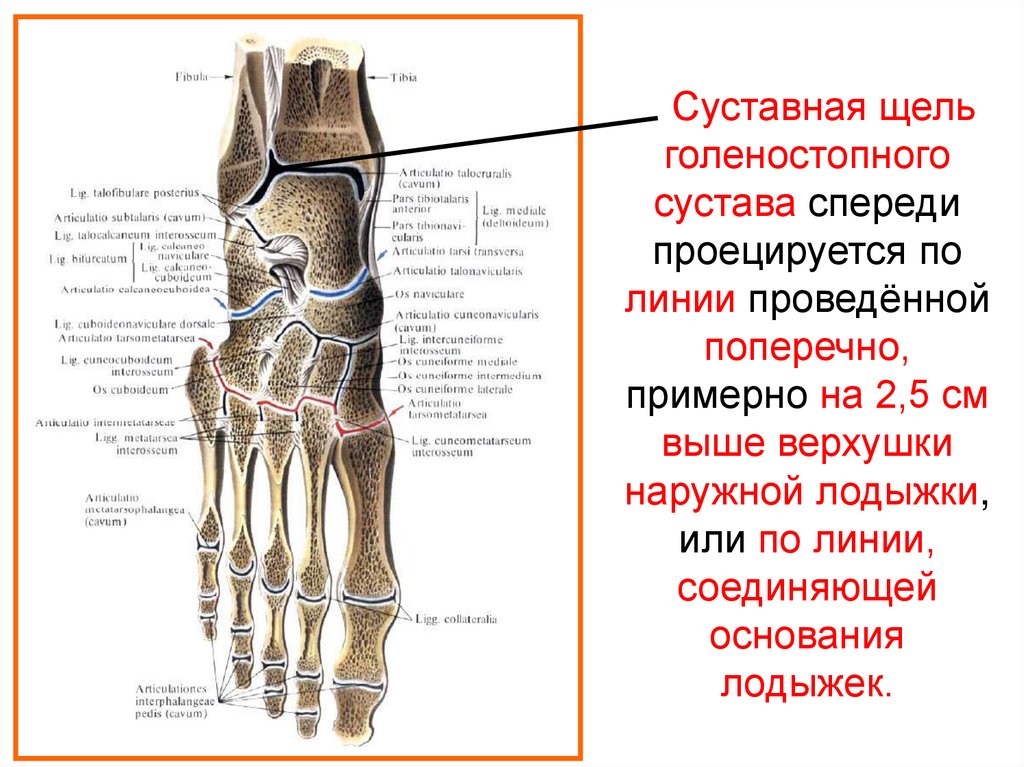

Анатомические фото голеностопного сустава и его суставных поверхностей